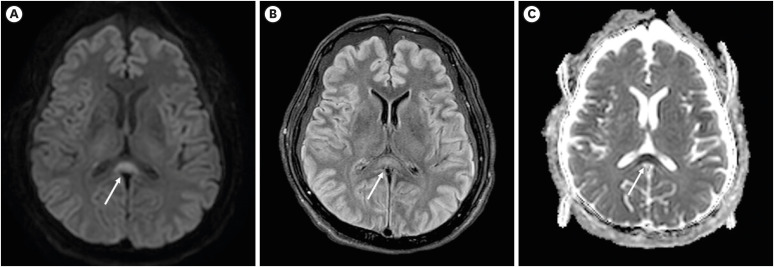

渗透性脱髓鞘综合征(ODS)是一种罕见的神经系统疾病与渗透失衡。传统上,已知ODS发生在低钠血症快速纠正之后;然而,ODS也被报道与高钠血症和高血糖有关。胼胝体细胞毒性病变(CLOCC)可由多种原因引起,包括药物、血管疾病、感染和代谢紊乱,如电解质失衡和血糖异常。ODS和CLOCC同时发生的情况极为罕见。在这里,我们报告了一例57岁男性,最初通过严重高钠血症和高渗性高血糖状态(HHS)发展为CLOCC,随后也被确定为ODS。医生应该知道CLOCC可能是与严重高钠血症和HHS相关的ODS的早期放射学发现。因此,在这些患者中应考虑积极的脑成像,以促进早期发现神经系统并发症。

Osmotic demyelination syndrome (ODS) is a rare neurological disorder associated with osmotic imbalances. Traditionally, ODS has been known to occur following the rapid correction of hyponatremia; however, ODS has also been reported concerning hypernatremia and hyperglycemia. Cytotoxic lesions of the corpus callosum (CLOCC), identified using transient magnetic resonance imaging, can arise from various causes, including drugs, vascular diseases, infections, and metabolic disturbances such as electrolyte imbalances and dysglycemia. The simultaneous occurrence of ODS and CLOCC is extremely rare. Here, we report a case whereby a 57-year-old male initially developed CLOCC via severe hypernatremia and hyperosmolar hyperglycemic state (HHS) was also subsequently identified with ODS. Physicians should know CLOCC may be an early radiologic finding in ODS associated with severe hypernatremia and HHS. Therefore, proactive brain imaging should be considered in these patients to facilitate the early detection of neurological complications.